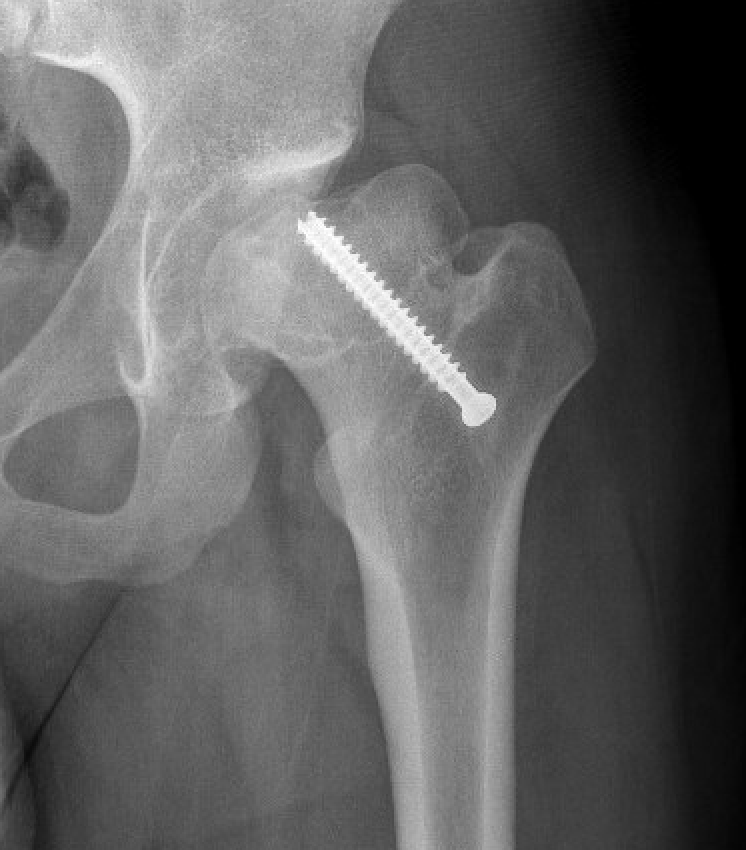

Cam FAI

Mechanism

Epiphysis heals in a posterior and inferior position with moderate - severe slips

Abnormal contact of relatively anterior neck on the acetabulum

Options

Arthroscopic osteochondroplasty

Open surgical dislocation and osteochondroplasty

Osteotomy